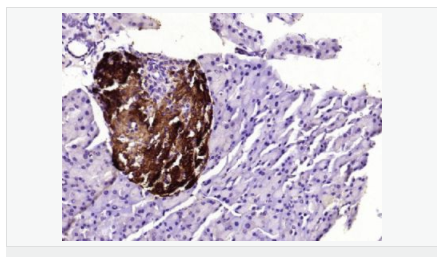

產(chǎn)品應(yīng)用WB=1:500-2000 ELISA=1:5000-10000 IHC-P=1:100-500 IHC-F=1:100-500 ICC=1:100-500 IF=1:100-500 (石蠟切片需做抗原修復(fù))

免 疫 原KLH conjugated synthetic peptide derived from human Sepiapterin reductase:101-200/261